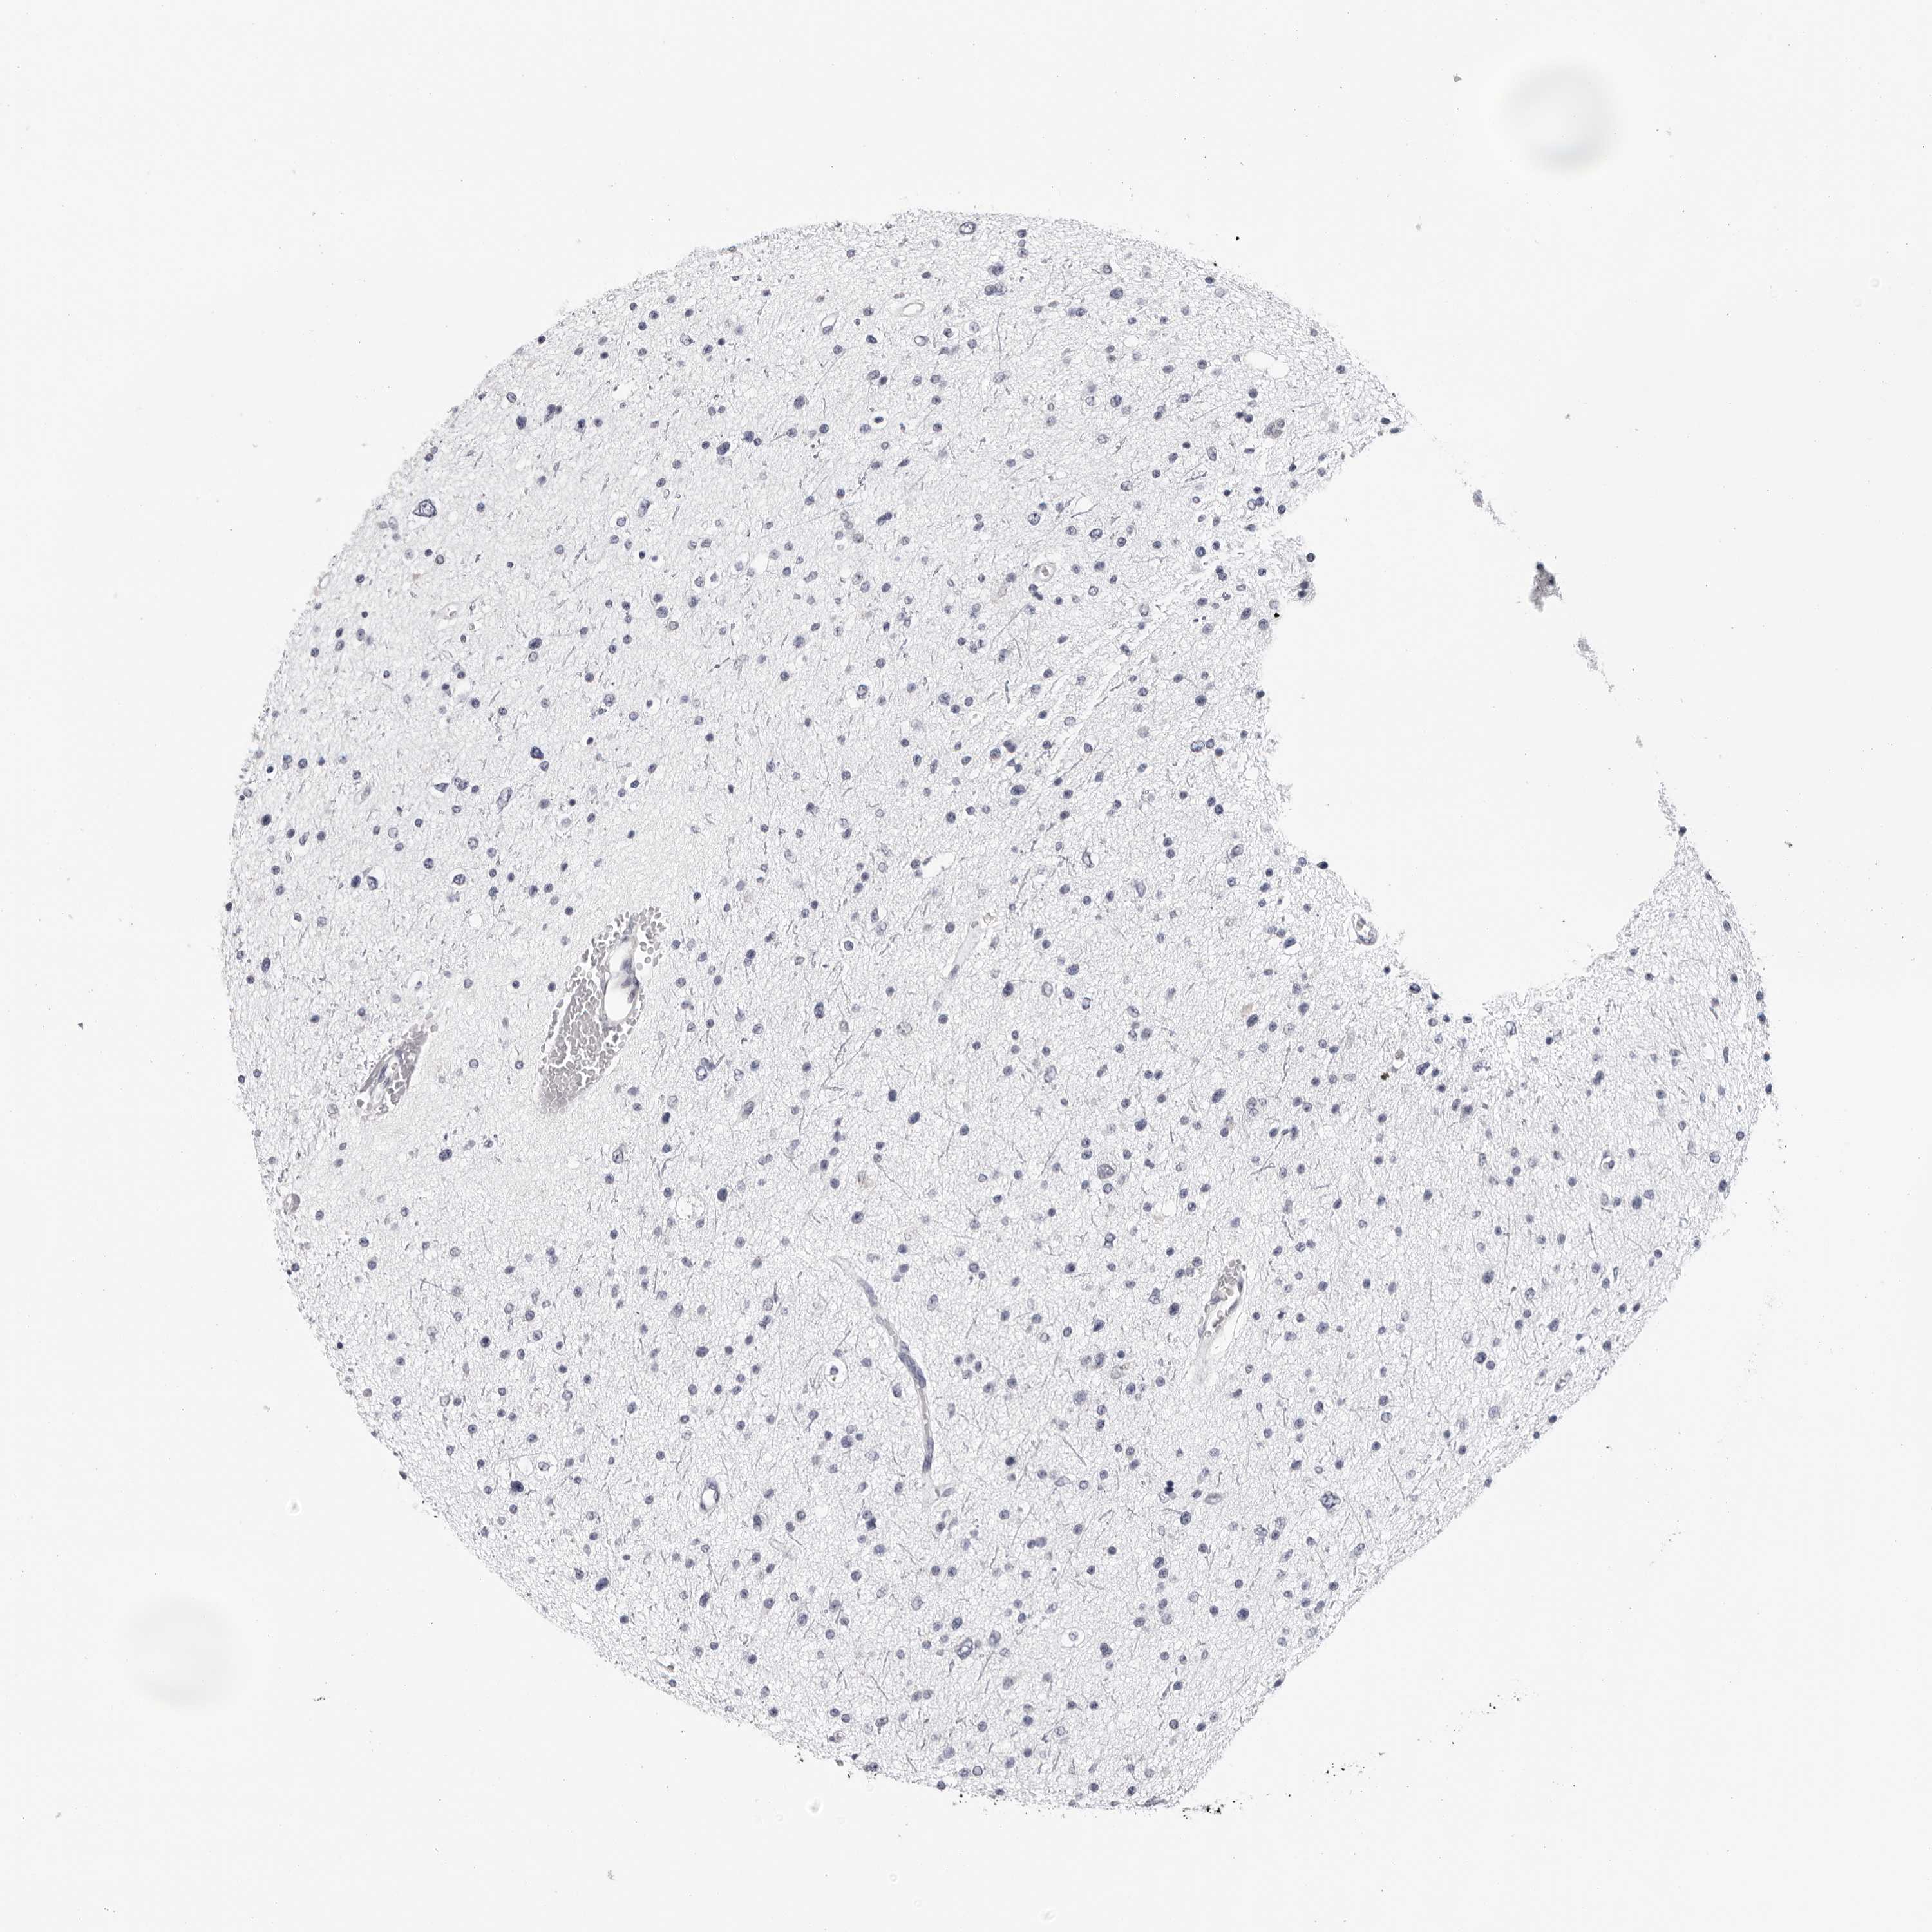

GLIOMA - Protein expressioni

A mouse-over function shows sample information and annotation data. Click on an image to view it in a full screen mode. Samples can be filtered based on level of antibody staining by selecting one or several of the following categories: high, medium, low and not detected. The assay and annotation is described here.

Note that samples used for immunohistochemistry by the Human Protein Atlas do not correspond to samples in the TCGA dataset.

Antibody stainingi

Antibody staining in the annotated cell types in the current human tissue is reported as not detected, low, medium, or high, based on conventional immunohistochemistry profiling in selected tissues. This score is based on the combination of the staining intensity and fraction of stained cells.

Each image is clickable and will lead to virtual microscopy that enables deeper exploration of all samples and also displays staining intensity scores, fraction scores and subcellular localization as well as patient and tissue information for each sample.

Antibody HPA024761

Antibody HPA029557

Staining

High

Medium

Low

Not detected

Intensity

Strong

Moderate

Weak

Negative

Quantity

>75%

75%-25%

<25%

None

Location

Nuclear

Cytoplasmic/membranous

Cytoplasmic/membranous,nuclear

Glioma, malignant, High grade

Glioma, malignant, Low grade

Glioblastoma, NOS